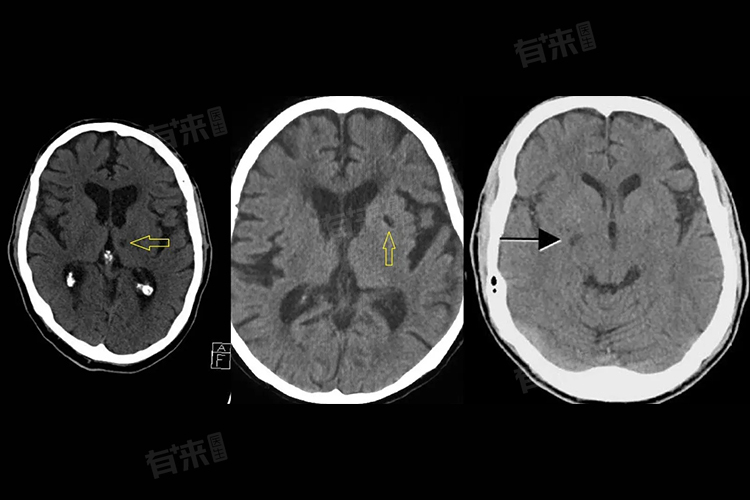

腔梗,即腔隙性脑梗死,是一种常见的脑血管疾病,由于血管堵塞导致脑部局部供血不足,进而引发脑组织缺血、缺氧。腔梗是否会导致走路不稳,需要根据具体情况进行评估。如果腔隙性脑梗死发生在与平衡和运动协调相关的区域,或者梗死灶较大、数量较多,可能导致走路不稳等症状的出现。但并非所有的腔隙性脑梗死都会导致走路不稳,具体症状还需根据患者的具体情况进行判断。

- 但如果腔隙性脑梗死发生在与平衡和运动协调相关的区域,如小脑、脑干等,这些区域负责身体的平衡和运动控制,受损后可能导致共济失调,表现为行走时摇晃、步态不稳、容易向一侧偏斜或倾倒。另外,腔隙性脑梗死的严重程度也会影响其症状表现。

如果梗 死灶较大或数量较多,对脑组织的影响也会更严重,从而增加出现走路不稳等症状的风险。对于腔隙性脑梗死患者,无论症状轻重,都应及时就医并接受专业治疗,以减轻症状、控制病情并预防并发症的发生。